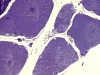

N. Semithin |

On hematoxylin-eosin stained sections, there is an increased variation of fiber diameter with many atrophic fibers intermingled with fibers of normal caliber. There is no evidence of fiber grouping or perifascicular atrophy. No inflammatory cells are present. There is also mild interstitial fibrosis (Panel A). On higher magnification, many fibers have a round concentric structure (Panel B). Irregular, centrally located depositions are also identified on modified Gomori's trichrome. The concentric nature, however, is not as obvious as in the hematoxin-eosin stained sections (Panel C). Type I and II fibers are not clearly separated in the ATPase preparation at pH 9.4. This is a common situation in chronically ill muscle (Panel D). The type I fibers are unusually dark. There is an increase in the proportion of type I fibers. The atrophic fibers are usually type II fibers. The concentric lesions are found predominantly in type I fibers (Panel E). There is an increase in PAS staining which is consistent with increased glycogen storage (Panel F). No increase in lipid content is demonstrated by oil red O (Panel G). On NADH-TR reaction, the concentric structures appear to have a clear central core that is devoid of enzymatic activity, a rim with intense enzymatic activity and a surround zone with relatively normal reactivity. These features are classic for target fibers (Panel H and I). No deficiency of laminin-2 (merosin) (Panel J) or dystrophin (Panel K) is demonstrated by immunohistochemistry. The central lesions are also immunoreactive for both laminin-2 and dystrophin. Immunohistochemistry for desmin demonstrate a core of strong immunoreactivity and also strong reaction in the sarcoplasmic membrane (Panel L and M). The target structures are also well demonstrated on semithin sections (Panel N). On electron microscopy, z-disc streaming is a common finding and they are often admixed with a substantial amount of dense granular electron dense substance (Panel O and P). There are also numerous cytoplasmic bodies characterized by radiating intermediate filaments (spheroid bodies) (Panel Q and R).